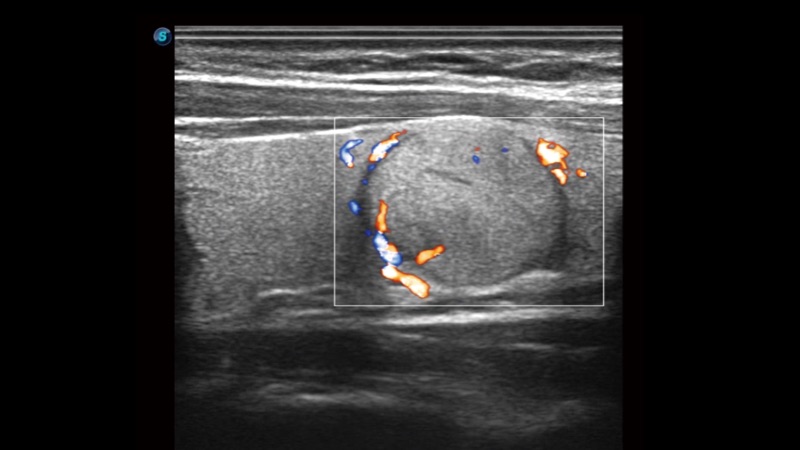

開立醫(yī)療通過不斷的技術(shù)創(chuàng)新,為大眾的生命健康提供持續(xù)關(guān)愛。P12 Plus采用全新一代超聲成像平臺,新平臺旨在將真實還原組織解剖結(jié)構(gòu)作為首要目標(biāo)。平臺采用全新集成化硬件模塊,搭載新一代芯片,系統(tǒng)性能得到大幅提升,為您的診斷提供了豐富的臨床信息。優(yōu)異的圖像表現(xiàn),豐富的探頭配置,全面的應(yīng)用功能,為您日常診斷提供了可靠的助手。

彩色多普勒超聲診斷系統(tǒng)